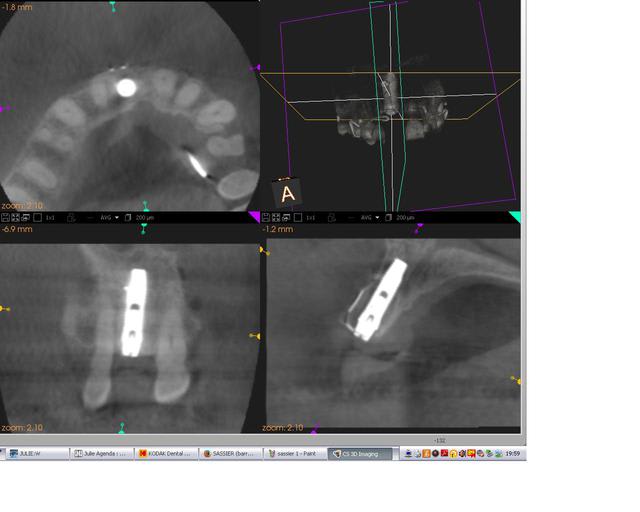

pour finir vous avez la 3D post op

3dpreop trkgfm - Eugenol

3dpostop tkiukd - Eugenol